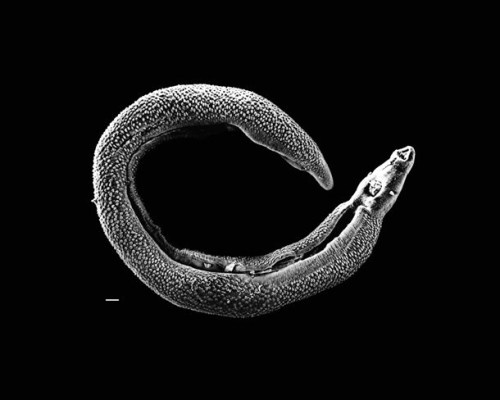

| 3. Sán dây trong ruột: Sán dây là những sinh vật ký sinh thường được tìm thấy trong ruột của con người và chúng có thể sống đến 25 năm trong đó. Tính trung bình, sán dây ở người dài một vài mét, nhưng trường hợp sán dây dài nhất từng được tìm thấy dài tới 25 m. |